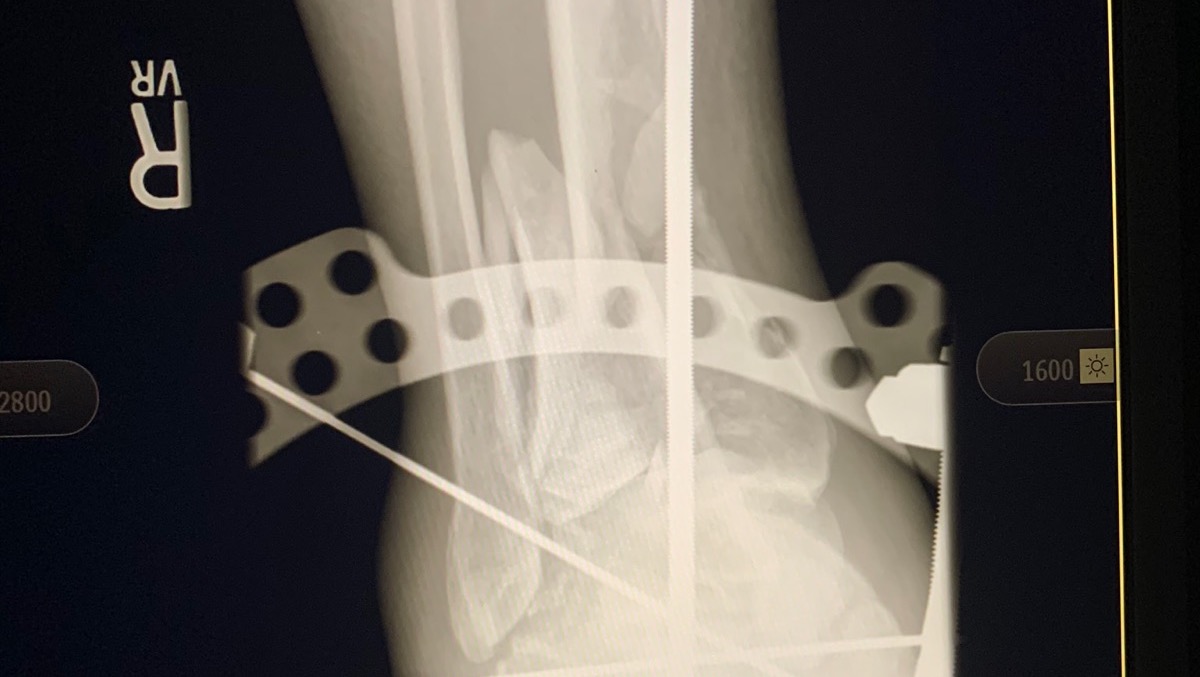

CAUTION : ( Graphic photos included)

In 2007, I was in a near fatal accident and fell off of a 20 foot bridge. I was rushed to the hospital where they put me in a drug induced coma for two weeks. When I woke up I had an “external fixator” on my right leg and foot with rods and pins sticking out everywhere. My right tibia and fibula were broken and both feet were shattered. My left foot had a steel plate secured with seven screws. My right foot had an “Ex-fix” secured with rods and pins. My left wrist was shattered and required five pins to put back together. My back was broken as well and had to be fused together at L4-S1 with more rods and screws.

As you can see, I had a really bad day! I subsequently spent  three years in a wheelchair before my right leg and foot were strong enough for the fusion surgery that I had in January 2010. It was then a steel plate and ten screws were put in my right foot. So that gets me out of the wheelchair, but I had to learn how to walk again. That is, I had to learn coordination / balance skills all over again.